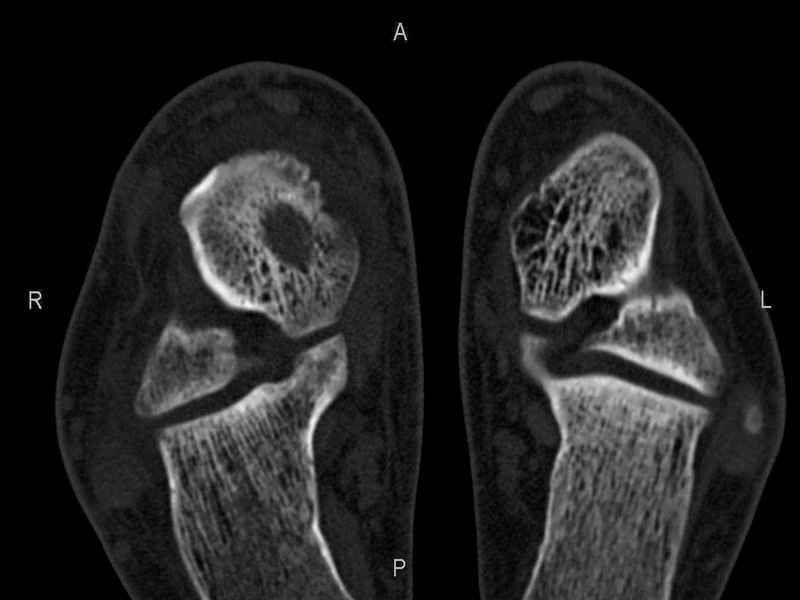

[Ortho] Рассекающий остеходрит + киста шейки тарана

Уважаемые коллеги, обратился за помощью пациент, мужчина, 25 лет. С жалобами на болевой

синдром в области голеностопного сустава и среднем отделе стопы. Травму отрицает. Со слов,

болевой синдром в течении 1 года. Последние 1-1.5 мес периодически вынужден пользоваться

костылями. После ограничения нагрузки боли уменьшаются. Соматически здоров. До появления

болей активно занимался рукопашным боем.

На СКТ картина рассекающего остеохондрита блока

таранной кости, киста шейки таранной кости с признаками импрессии суставной поверхности. А

также - разрастания переднего края б\берцовой кости сопровождающиеся клиникой импиджмент

синдрома.